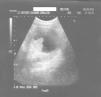

Observación clínicaMujer de 16 años, fumadora, sin antecedentes personales ni familiares de interés, que acudió a consulta por un cuadro de dolor abdominal difuso, más intenso en fosa ilíaca izquierda, de 24 h de evolución, que relacionó con la ingesta de golosinas el día previo. La anamnesis por órganos y aparatos fue anodina. En la exploración física presentaba dolor localizado en fosa ilíaca izquierda, sin signos de peritonismo. Se realizó ecografía abdominal, y se observó una imagen quística en anexo izquierdo, de 90mm, anecoica, con área intraquística hiperecogénica de bordes irregulares. Se remitió al servicio de ginecología, donde realizaron RM y la diagnosticaron de posible cáncer de ovario. Fue intervenida quirúrgicamente realizándosele anexectomía izquierda. El estudio anatomopatológico reveló cistadenoma seroso de 9cm con región borderline en su interior. Se decidió seguimiento sin realizar tratamiento adyuvante.

Seidman et al10, en una revisión bibliográfica de los TBO de tipo seroso, muestran que el 16% de las pacientes en estadios II y III tuvieron recurrencia o fallecieron por la enfermedad. Para Massad et al14, el 6% de las pacientes en estadio II y el 21% en un estadio superior fallecieron. La presencia de tumor invasivo peritoneal reduce la tasa de supervivencia entre un 30 y un 50%15. En una reciente revisión se encontró una transformación en cáncer invasivo en el 7% de los casos de TBO seguidos durante al menos 5 años16. La imagen ecográfica de los TBO suele ser una imagen quística multilocular, con septos o de ecogenicidad mixta17. En la fig. 1 se puede apreciar la imagen ecográfica de esta observación clínica, consistente en un quiste de 90mm, de contenido anecoico, con refuerzo acústico posterior, hacia cuyo interior se proyecta una formación ecogénica.